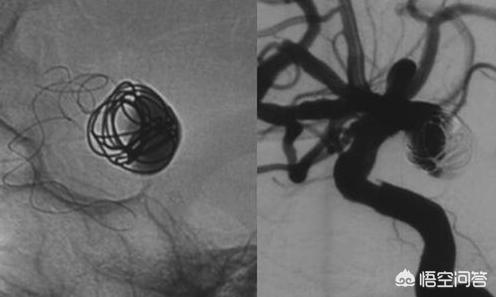

Es ist eines der am häufigsten verwendeten Medikamente bei radiologischen Eingriffen, vor allem bei der Darstellung von Blutgefäßen und Körperhöhlen.

Dies liegt daran, dass die Herzgefäße selbst bei der Koronarangiographie nicht sichtbar gemacht werden, da sie aus weichem Gewebe bestehen und Röntgenstrahlen beim Durchdringen nur selten absorbiert werden, so dass es schwierig ist, ein Bild von ihnen zu erhalten.

Aber so wie wir einem klaren Wasserstrahl Tinte hinzufügen können, um ihn besser sehen zu können, können wir das Blut mit Kontrastmitteln "einfärben" (die Röntgenaufnahme erhöhen).

Derzeit werden in der klinischen Praxis hauptsächlich zwei Arten von Kontrastmitteln verwendet: jodhaltige Kontrastmittel und Walzenkontrastmittel. Jodhaltige Kontrastmittel werden hauptsächlich für die Röntgenbildgebung, einschließlich CT, DSA (digitale Silhouettenangiographie, Koronarangiographie und Lebertumor-Arteriographie) usw. verwendet, während gerollte Kontrastmittel hauptsächlich für die Magnetresonanztomographie eingesetzt werden.